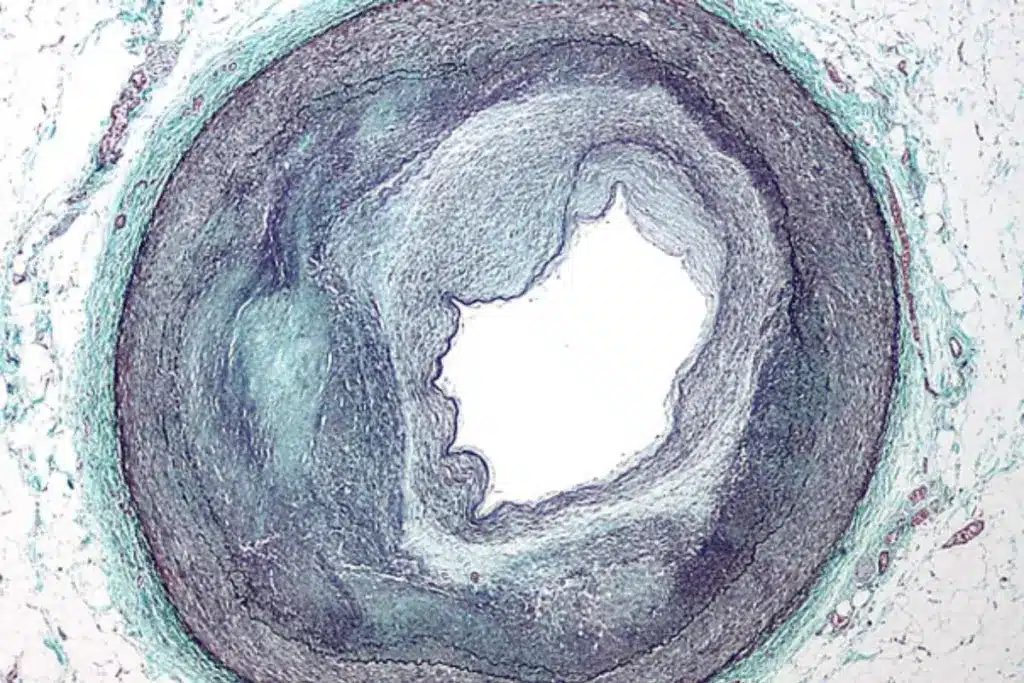

Coronary angiography is a way to see inside the heart’s arteries. It helps doctors find blockages or problems. This test gives a clear view of the arteries.

Coronary angiography uses X-rays to look at the heart’s arteries. A special dye is put into the arteries through a thin tube. This dye makes the arteries show up on the X-rays, helping doctors spot any issues.

This test is key for diagnosing heart disease. It shows how healthy the arteries are. Doctors use this info to decide the best treatment.